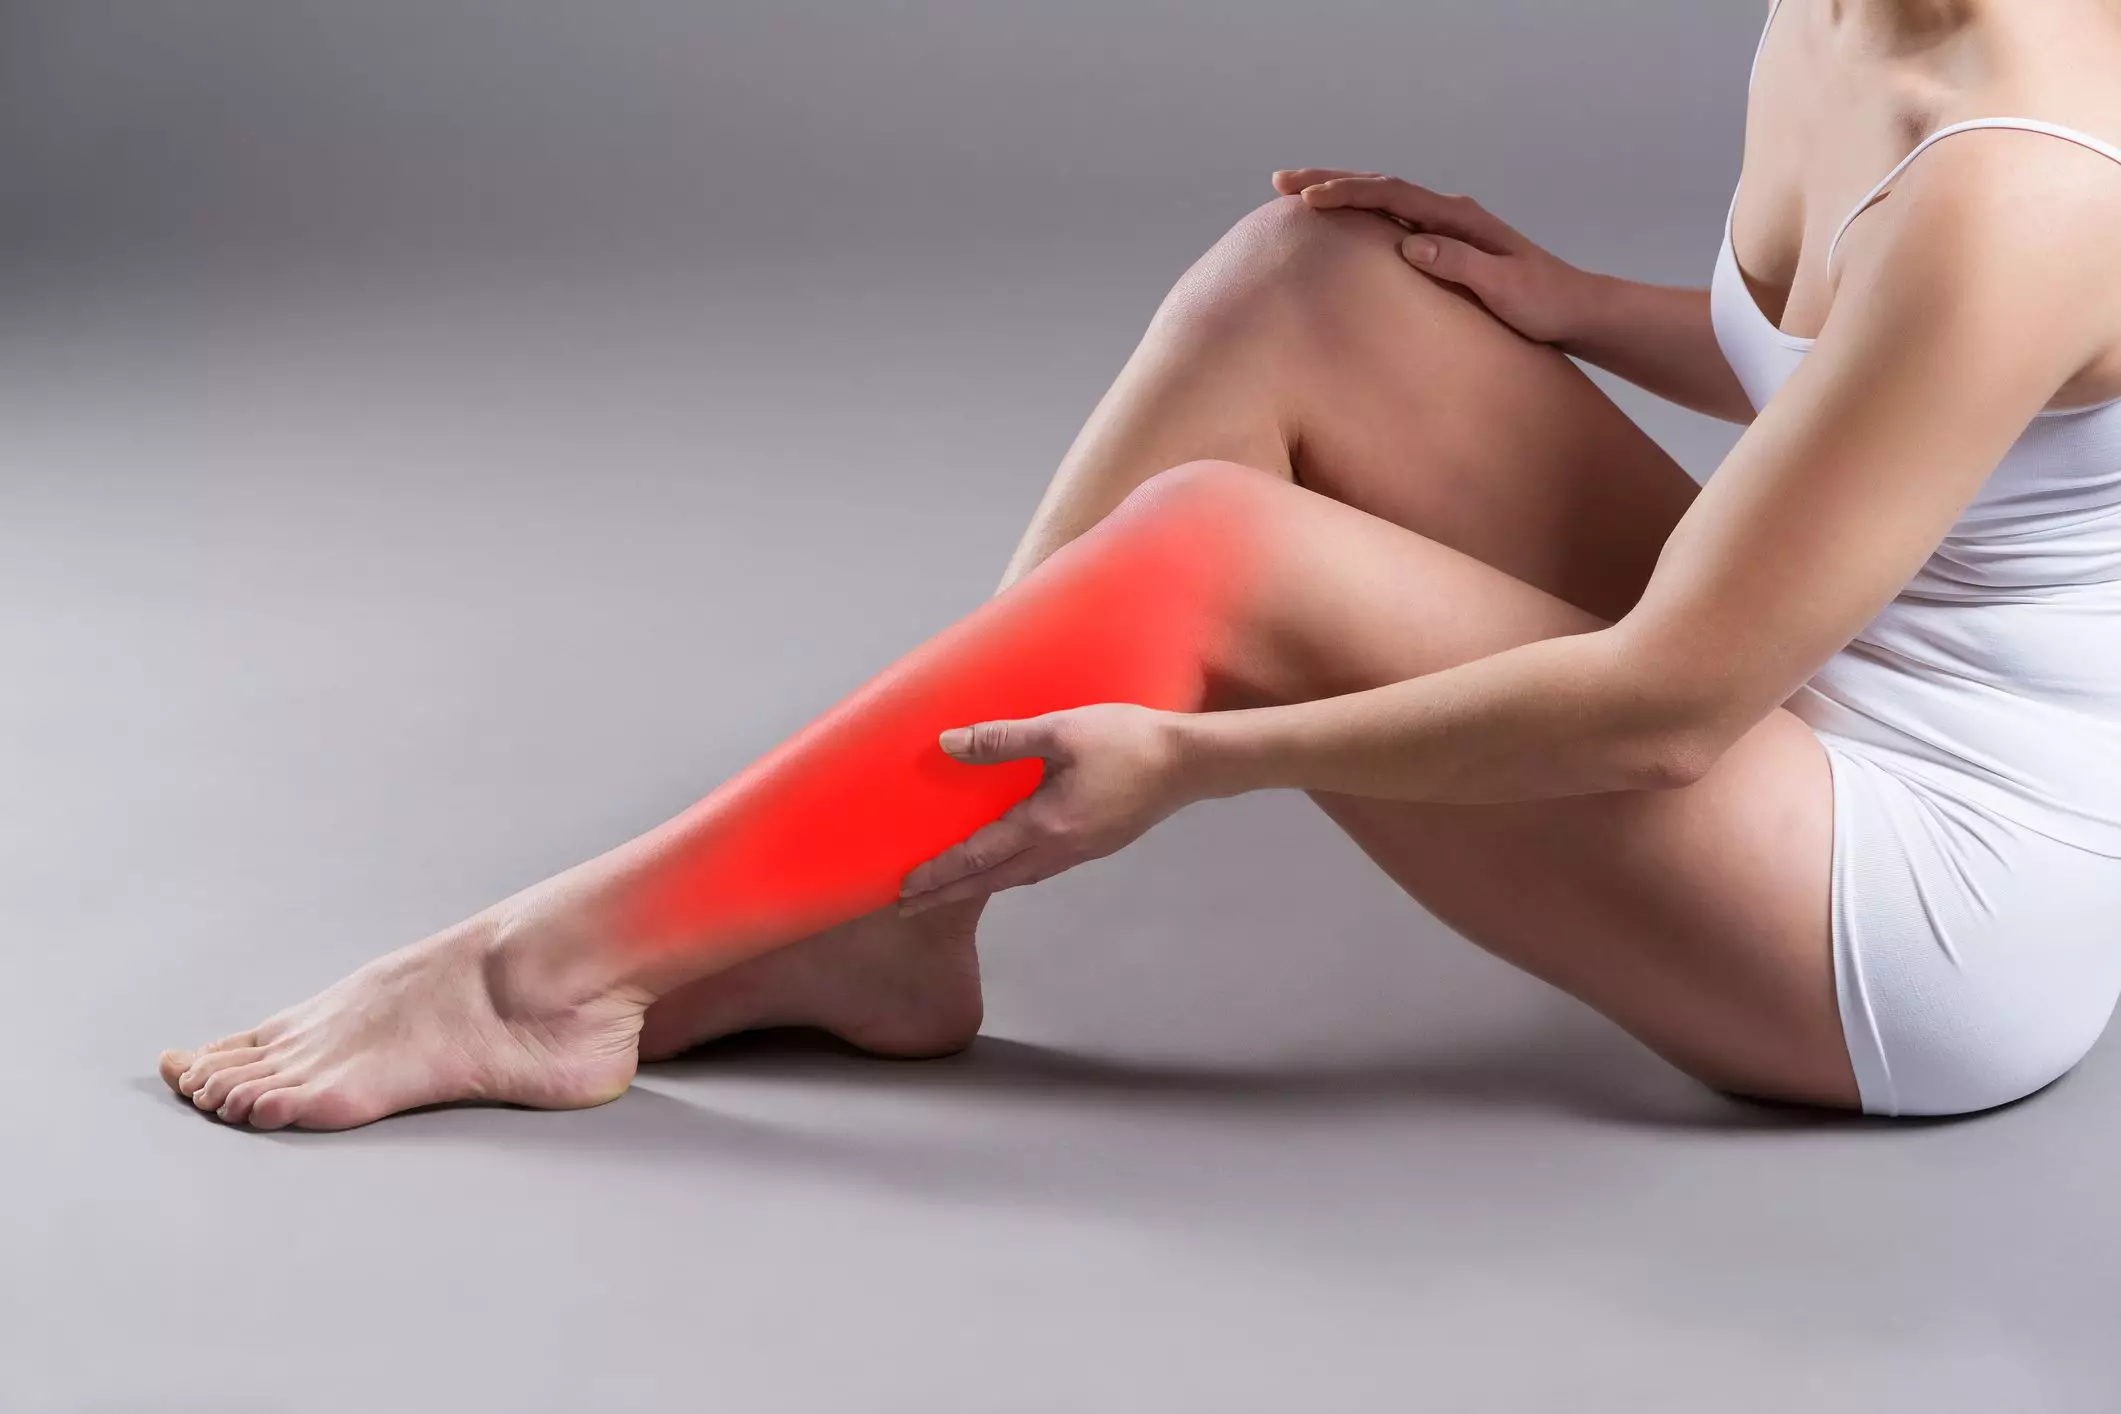

Причины судорог в ногах и способы их устранения